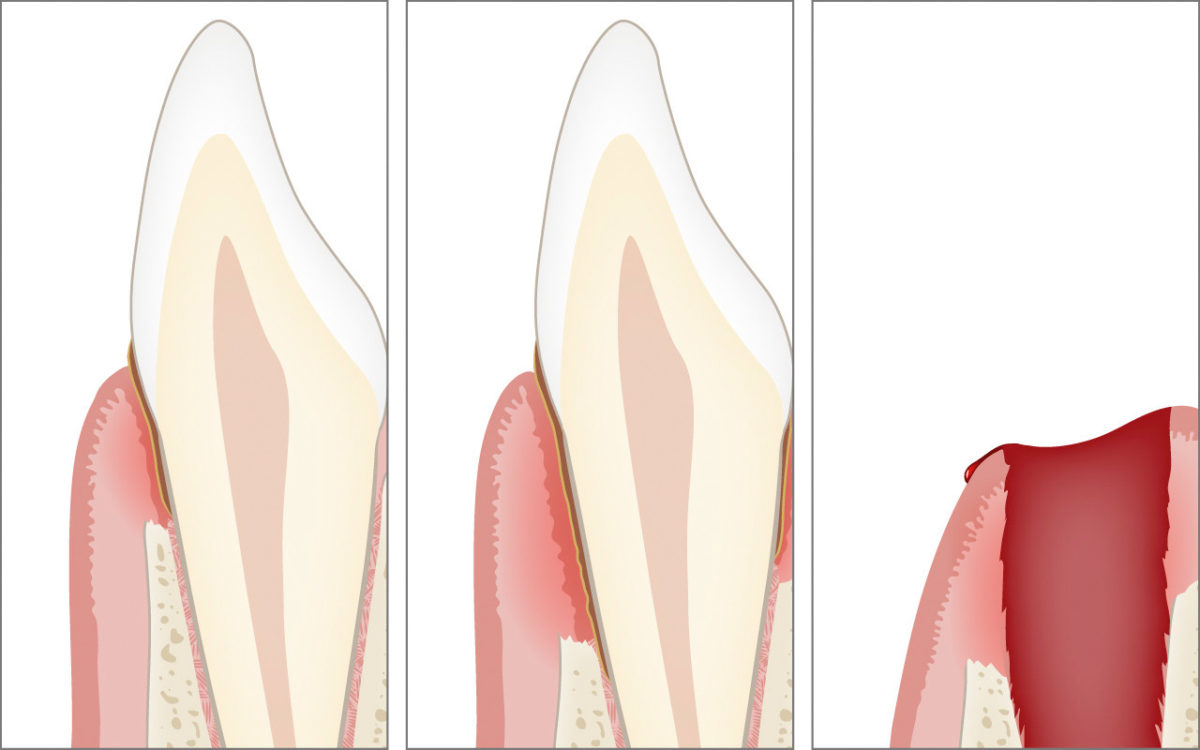

Knochenverlust, Zahnfleischtaschen und Zahnverlust

Durch die bakterielle Entzündung der Parodontitis wird die Zahnverankerung abgebaut. Die Folgen sind die Bildung von Zahnfleischtaschen bis hin zum Zahnverlust.

Der Abbau der Zahnverankerung kann zu einer erhöhten Zahnbeweglichkeit führen. Die Zähne, welche normalerweise fest im Knochen verankert sind, verlieren an Stabilität und werden lose oder «wackelig».

Falls die Erkrankung unerkannt bleibt und nicht behandelt wird, kann sich der Abbau soweit fortsetzen, dass die Zähne in ihrer Funktion zum Kauen unbrauchbar werden und gezogen (extrahiert) werden müssen.